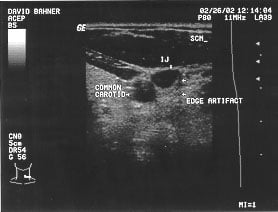

Procedures: internal jugular vein